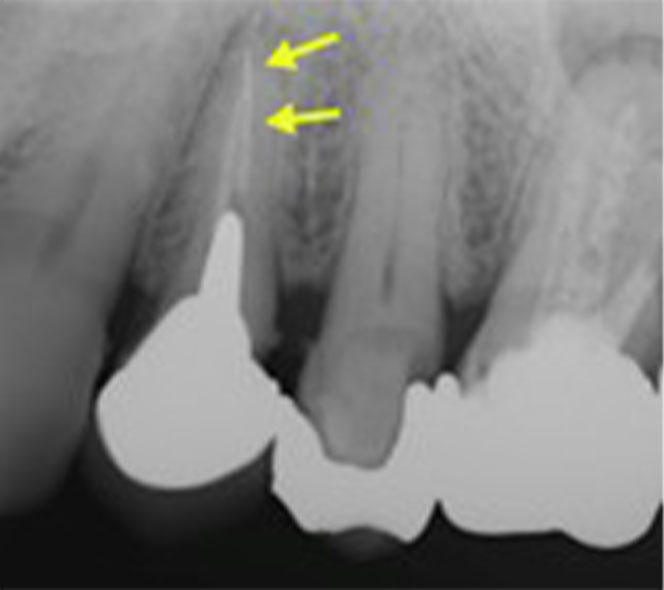

CBCTを用いた精密検査

当院は、歯科用に開発されたCTであるCBCTを備えています。

CBCTは医科用のヘリカルCTと比較して、①空間分解能(解像度)が高く、②放射線量(被ばく線量)が低いという特徴があります。

CBCTにより、2次元のレントゲン写真ではわからない3次元的な歯の構造を検査することが可能です。

歯内療法においては、根の構造を事前に把握することで、危険を回避したり、問題点を明らかにすることができます。その結果、安全に治療を進めることができ、治療の成功率の向上につながります。